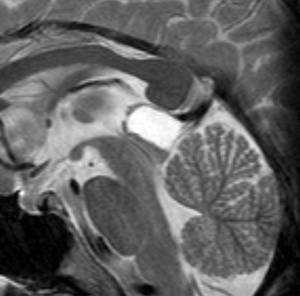

これも成人女性に偶然見つかった松果のう胞です。少し大きめですが,何も治療する必要はありません。中脳水道という所が狭くなっていますが,はっきり閉塞するまでは治療はしません。左がT1強調画像で黒っぽく見えます。右はT2強調画像で白く映っています。